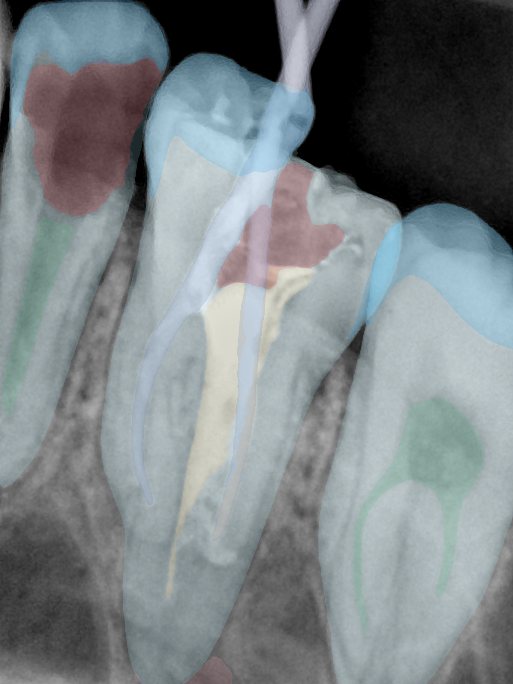

CR/DR 牙齿分割阶段记录

当前进展

- 完成了 CR/DR 牙齿相关分割训练

- 当前结果已经达到阶段预期,但仍有细节问题需要继续处理

相关测试

遇到的问题

- 训练过程中出现过 mask 下移问题

- 部分结果会出现 box 填充异常

- mask 边缘仍然有比较明显的锯齿感

参考

第二版算法问题测试